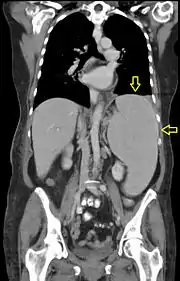

Splénomégalie (flèches jaunes) visible au scanner chez un patient atteint de leucémie myéloïde chronique